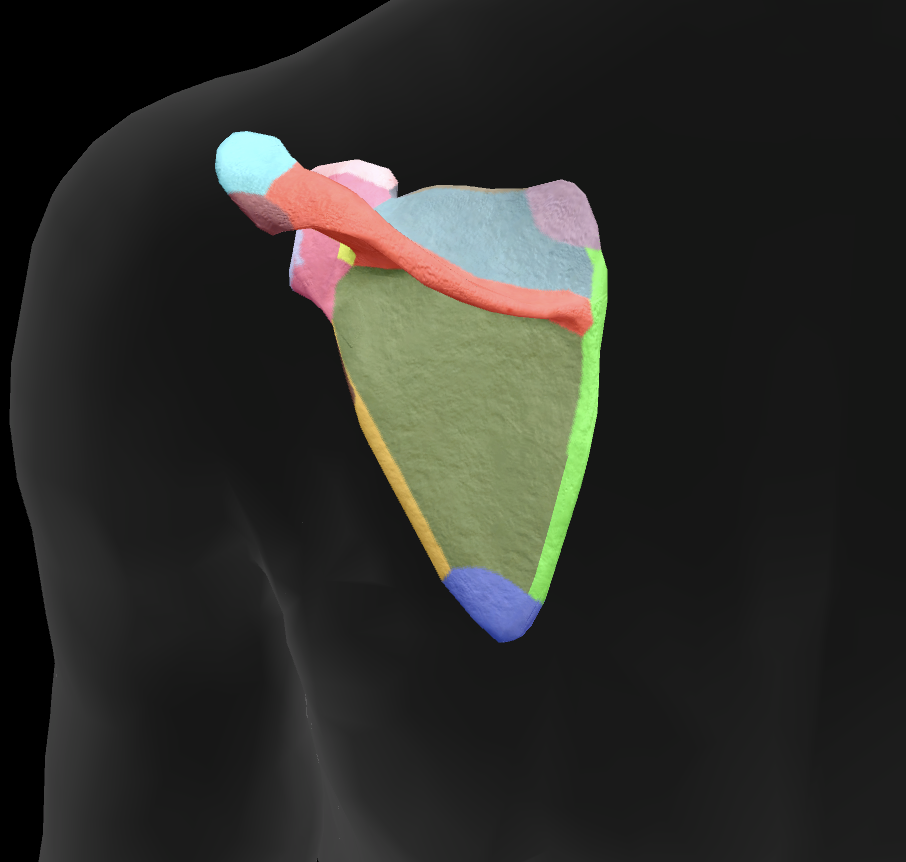

scapula

What is this boney landmark?

spine of scapula

What is this boney landmark?

supraspinous fossa

What is this boney landmark?

infraspinous fossa

What is this boney landmark?

acromion process

What is this boney landmark?

superior angle

What is this boney landmark?

inferior angle

What is this boney landmark?

lateral border

What is this boney landmark?

medial border

What is this boney landmark?

subscapular fossa

What is this boney landmark?

spinoglenoid notch

What is this boney landmark?

glenoid fossa

What is this boney landmark?

supraglenoid tubercle

What is this boney landmark?

infraglenoid tubercle

What is this boney landmark?

coracoid process

What muscle is this?

subscapularis

What muscle is this?

supraspinatus

What muscle is this?

infraspinatus

What muscle is this?

teres minor

What are the rotator cuff muscles?

supraspinatus, infraspinatus, teres minor, subscapularis